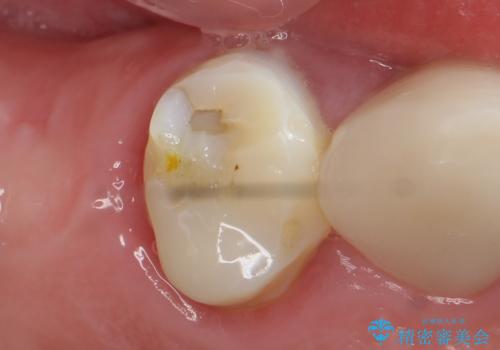

[フルジルコニアクラウン] 老朽化した銀歯を白く

![[フルジルコニアクラウン] 老朽化した銀歯を白くの症例 治療後](https://seimitsushinbi.jp/wp/wp-content/uploads/2020/05/60951366446f010978e24aba6c35e27e-500x350.jpg?v=1588518777)